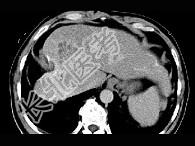

- 单项选择题女性,56岁, 腹胀、双下肢水肿、乏力、食欲不振,影像所见如下图, 最佳的诊断是  (    )

- A、酒精性肝硬化并肝血管瘤

- B、血吸虫肝硬化并肝癌

- C、肝炎后肝硬化并肝癌

- D、局限性脂肪肝

- E、原发性肝癌